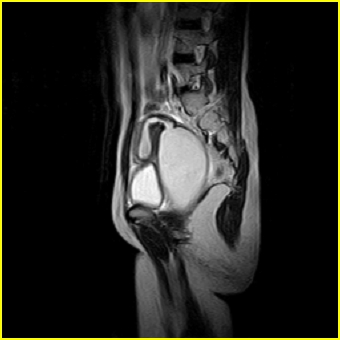

女、15岁、下腹疼痛2天,排尿困难1天。查体:处女膜闭锁,距处女膜约4至5cm处扪及一约5cm直径的圆形包块,张力较高,触痛明显、欠活动。b超提示子宫增大伴宫内增强回声团。

影像意见:子宫直肠陷凹积血。

更正影像意见:阴道积血。

处女膜闭锁,阴道积血

处女膜闭锁,阴道积血,子宫积血.

先天性处女膜闭锁,伴阴道积血,不除外先天性阴道粘液囊肿形成。

阴道积血,子宫积血.

子宫及阴道积血。

处女膜闭锁,伴子宫及阴道积血.